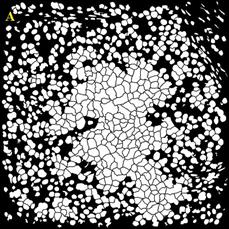

В ходе работы выполнен анализ трех изображений, с площадью покрытия клетками окна среза 80%; и 40%, а также наличия размытых границ клеток (Рисунок 3).

Рисунок

3 – Примеры обрабатываемых изображений. А – площадь покрытия клетками окна среза 80%; Б – площадь покрытия клетками окна среза 40%; В – наличия размытых границ клеток. Далее – изображения 1, 2, 3, соответственно

Для сравнения качества сегментации использовались маски ядер и клеток. Маски, полученные при помощи разработанного алгоритма, показаны на Рисунок 4.

4 – Результаты обработки изображений А – маска ядер изображения 1; Б – маска клеток изображения 1; В – маска клеток изображения 2; Г – маска клеток изображения 2; Д – маска ядер изображения 3; Е – маска клеток изображения 3

Разработанные алгоритмы показали хорошее качество сегментации для изображений с большим и малым количеством клеток. Однако алгоритм сегментации требует доработки при работе с нечёткими изображениями. В этом случае маска клеток содержит искаженные границы клеток для большинства ядер.

Количество клеток на первом изображении составляет 848, на втором 229, на третьем 218. Количество пропущенных либо раздробленных ядер и клеток не превышает 5% от общего числа клеток.